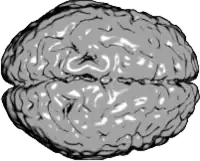

Vista superior del cerebro humano. La región anterior del cerebro (frontal) está a la derecha, el hemisferio izquierdo aparece arriba y el hemisferio derecho debajo. | ||